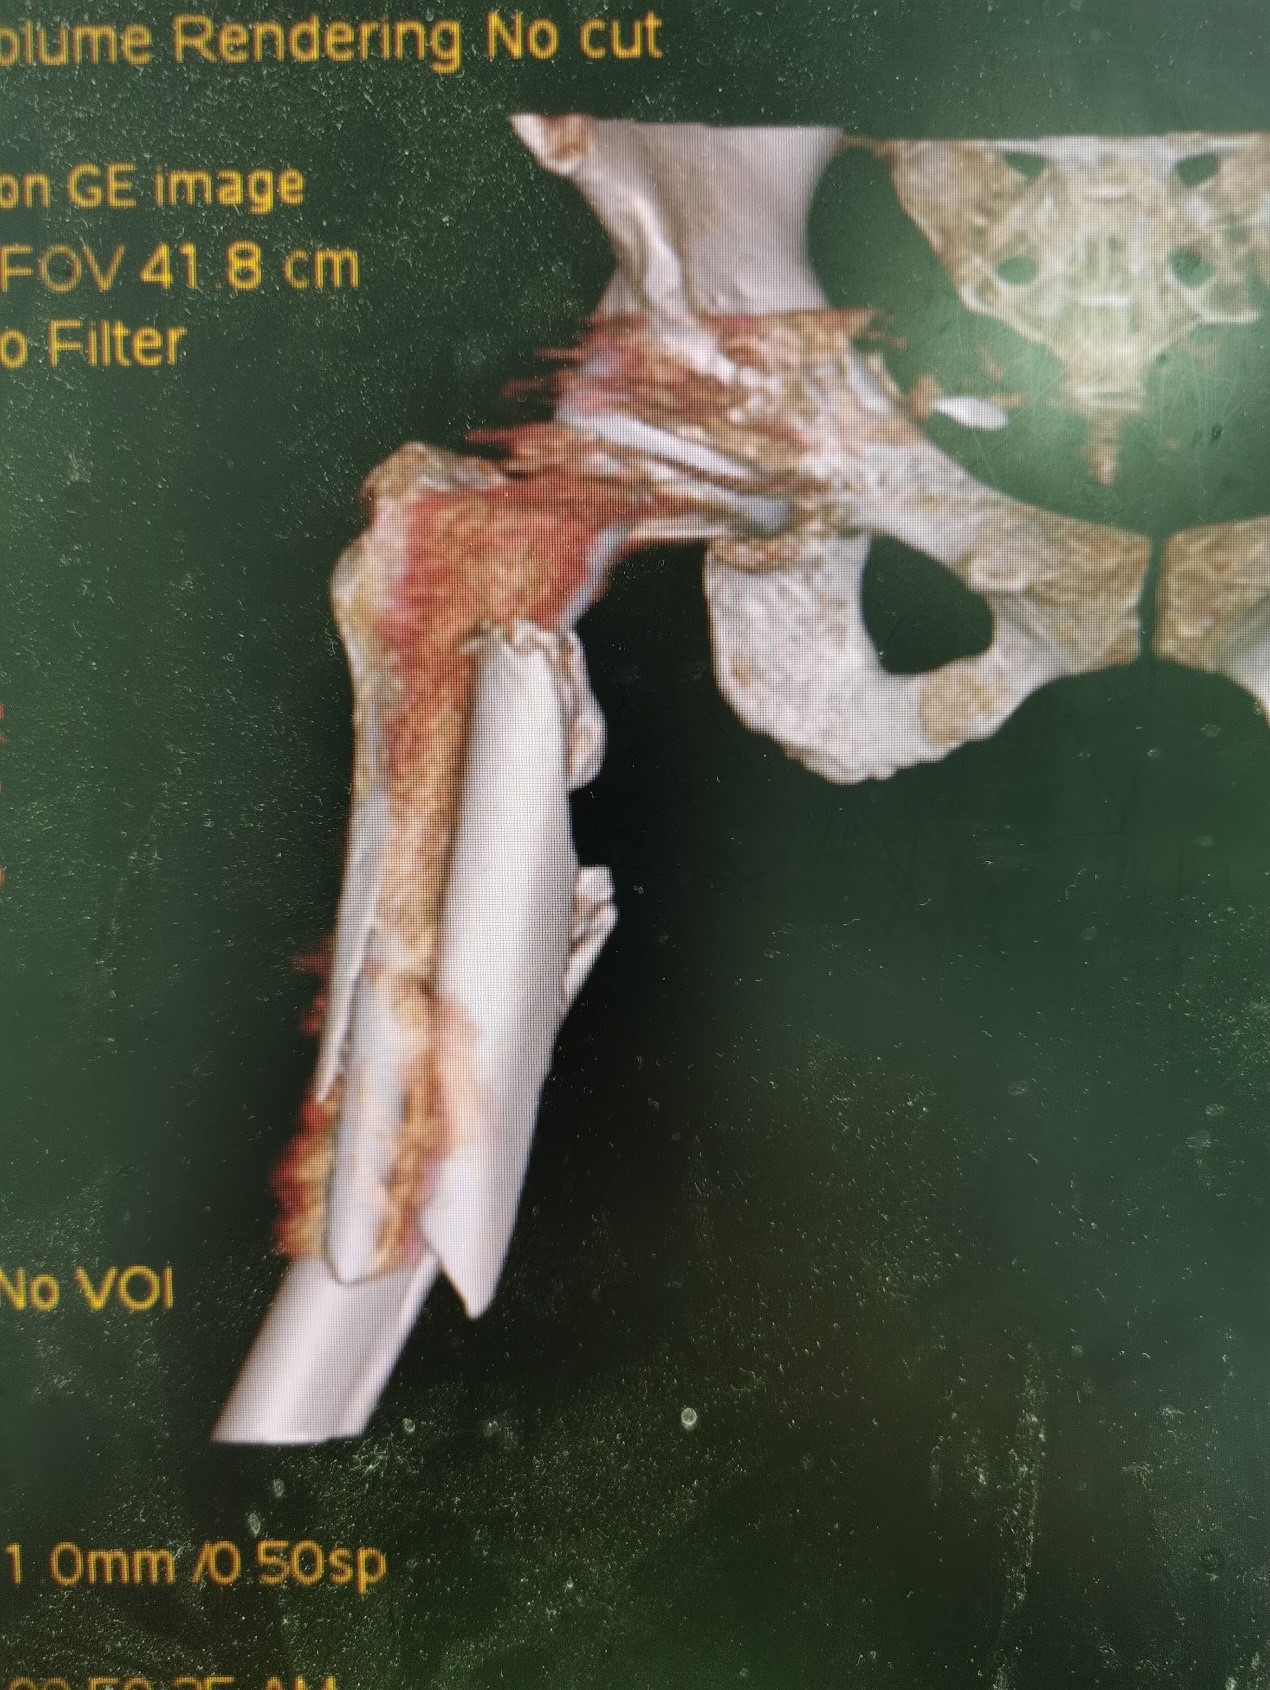

案例三:59岁女性假体周围骨折

患者情况:吴女士,5年前曾在我院接受人工髋关节置换术,近日因在家中地板湿滑处摔倒,导致假体周围骨折。

治疗难点:

1.摔伤后需评估假体是否松动;

2.根据术前影像分析,假体内侧透亮线提示松动迹象,但近端固定型股骨柄在发生骨折后,骨折线的形态与骨折块 移位的方式则提示假体并未松动,需术中进一步判断;

3.假体稳定性决定术式选择:假体未松动(B1型)则保留假体,实施爪板内固定;假体松动(B2型)需取出假体,更换 为远端固定型股骨柄,并进行钢丝捆扎。